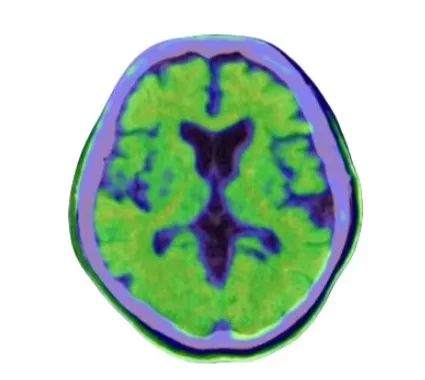

▲患者头颅Aβ PET-CT 阳性,提示异常淀粉样蛋白沉积